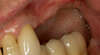

Vue préopératoire